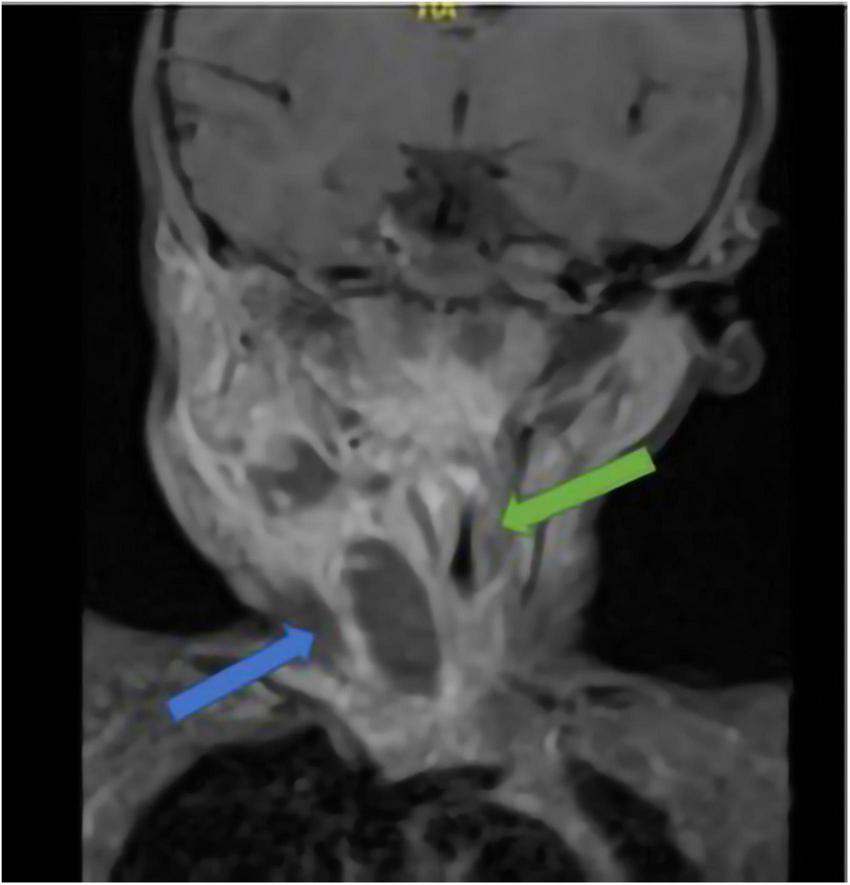

Cervical bulk was indurated, painful, and measured 3 cm on its long axis, at palpation. Initial blood analysis demonstrated a major inflammatory syndrome with a white blood cell count of 22,330/μl (with 16,190/μl absolute neutrophils) and a CRP of 180 mg/L. Indeed, a cervical MRI showed an abscess cavity measuring 10 cm long and 2 cm wide on a necrotic lymph node. This abscess extended to the anterior parapharyngeal space fusing to the middle mediastinum, next to cardiac vessels. Its massive extension reduced the size of the trachea (Figure 2).

FIGURE 2

Cervical MRI of case 2; blue arrow: abscess; green arrow: trachea stenosis.